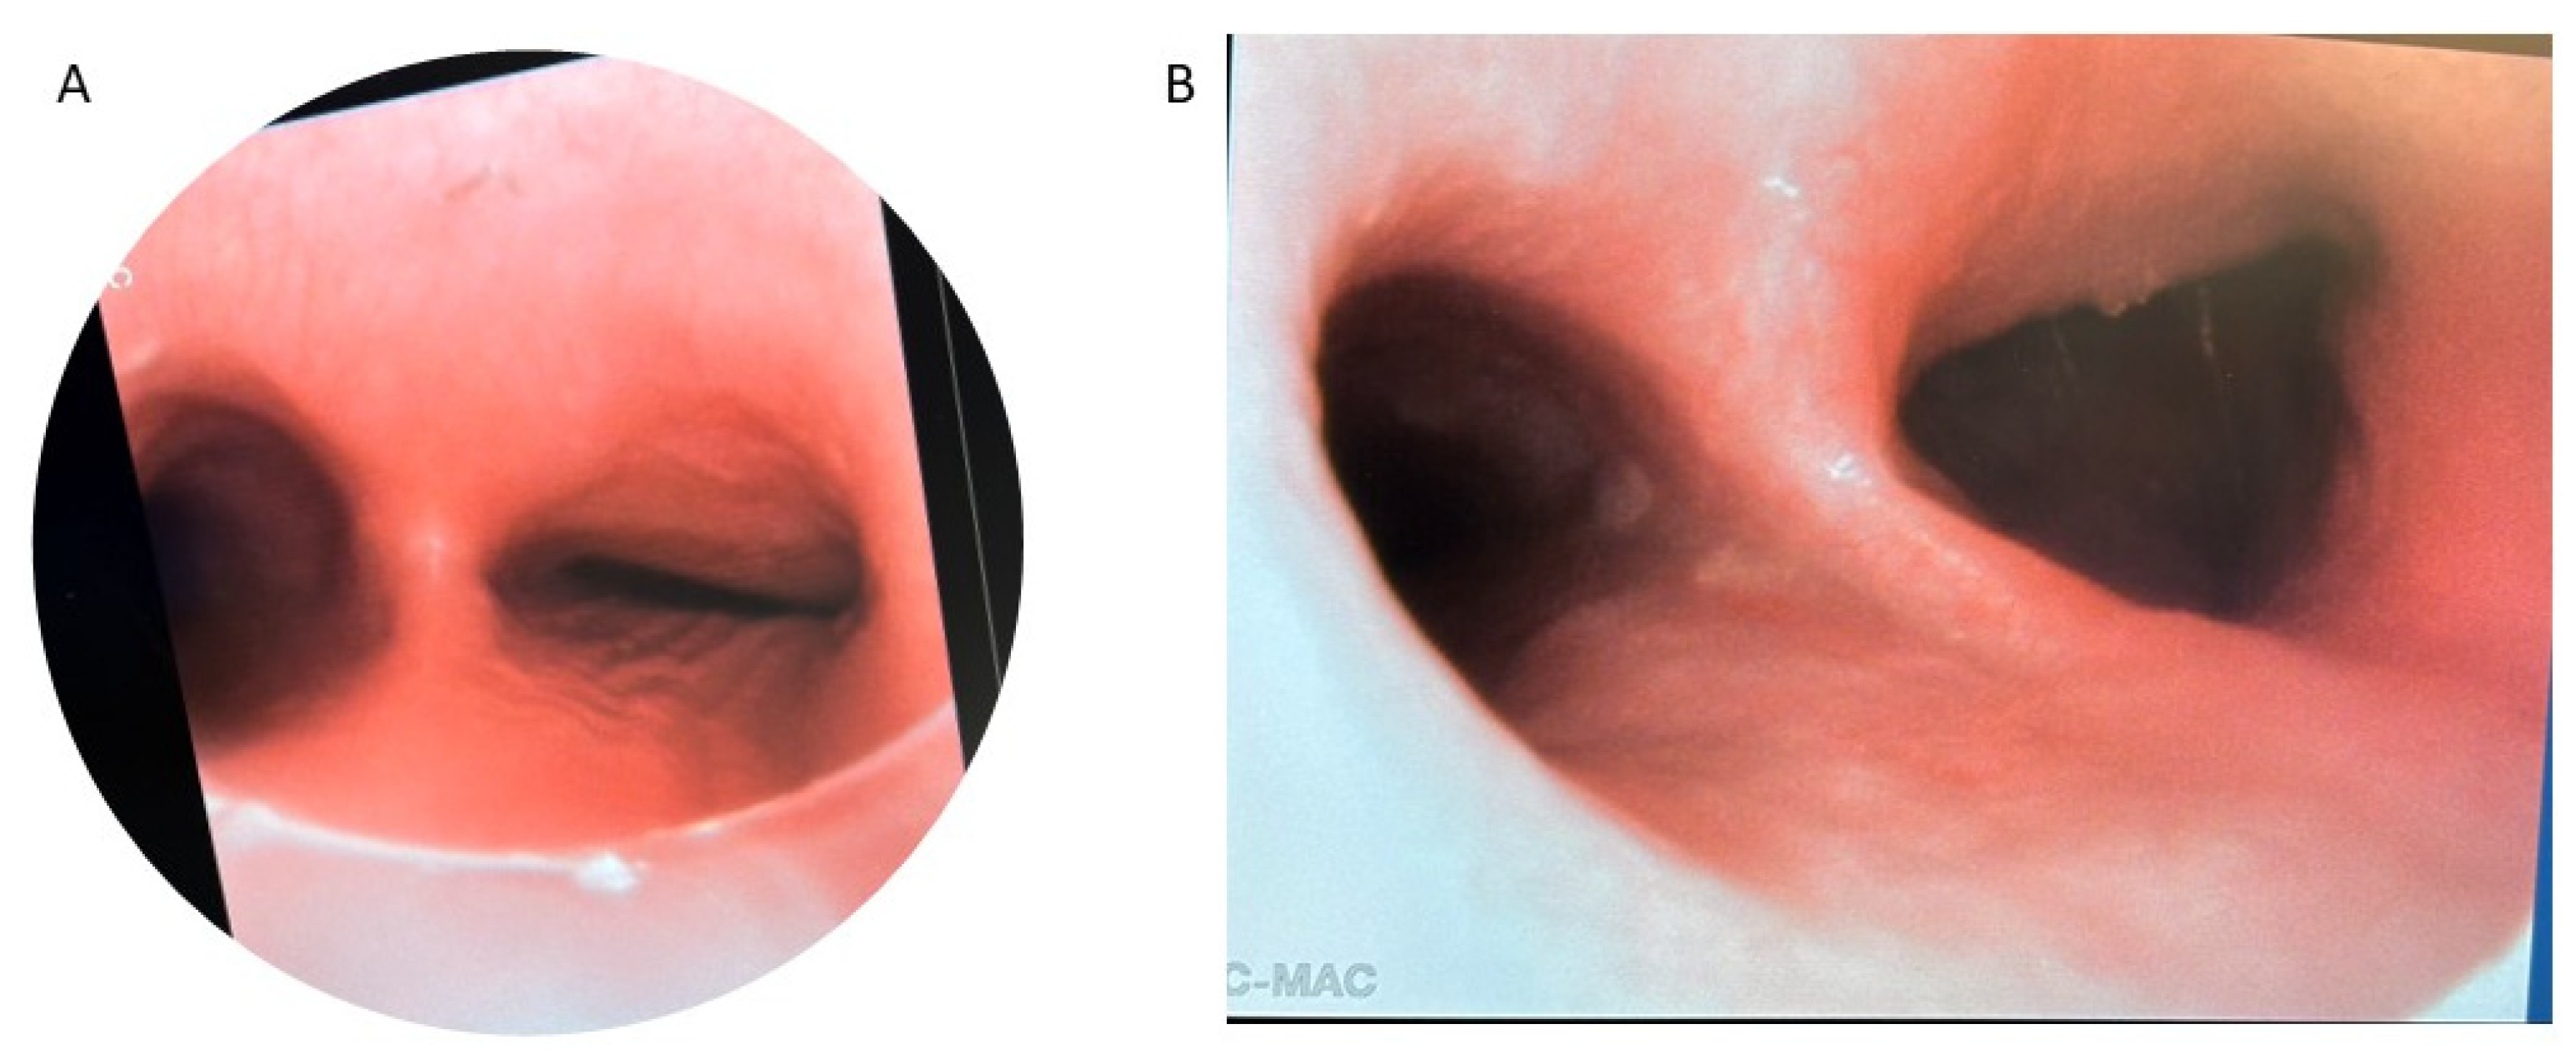

Patients with severe medically refractory cases of TM who are being considered for posterior tracheopexy should undergo thorough preoperative workup to ensure proper candidacy for this operation. Beyond the diagnosis and management of underlying associations (e.g., VACTERL in patients who previously underwent TEF/EA repair), patients should undergo “quadruple endoscopy”, incorporating laryngoscopy, dynamic bronchoscopy, distal bronchoscopy, and esophagogastroduodenoscopy (EGD) [9,13,15,19,21,29,30,31,32,33,34,35]. Laryngoscopy facilitates evaluation of the upper airway and any underlying vocal cord dysfunction that may be present preoperatively. Assessment of vocal cord function is particularly important in patients who previously underwent TEF/EA repair as they may have suffered a recurrent laryngeal nerve injury during the prior TEF/EA repair. Dynamic bronchoscopy is the gold standard in diagnosing TM and best informs the obstructive pattern present within the airway (Figure 2). Dynamic bronchoscopy is divided into 3 phases: shallow breathing, cough/Valsalva, and apneic [29]. In the first phase, patients are maintained with deep general anesthesia and allowed to spontaneously ventilate. The spontaneous ventilation phase allows for the assessment of basic airway anatomy, extraluminal compression, malformations, and secretion accumulation [36]. During the second phase, anesthesia is reduced and patients are permitted to cough, Valsalva, or otherwise vigorously breathe [29]. Observation of the airway during these increased intrathoracic pressures reveals the maximum dynamic airway collapse the patient may experience [36]. Dynamic inspection of the tracheal lumen during this period of increased intrathoracic pressure delineates the directionality of tracheal collapse and assists in the selection of an anterior or posterior surgical approach. Observation of an anterior collapse may indicate compression by an aberrant innominate trunk or otherwise aberrant anatomy, whereas posterior intrusion is more indicative of a hypermobile pars membranacea. Finally, for the apneic phase of the dynamic bronchoscopy, patients are deeply sedated again and the airways are distended to 40–60 cm H2O, which allows for identification of lesions such as TEF, tracheal diverticulum, and aberrant bronchi [36]. Distal bronchoscopy aids in the diagnosis of more distal TBM that may be less amenable to extraluminal surgical intervention. Standardized endoscopic TM scoring systems have previously been described which quantify the proximal and distal airway mobility seen during a dynamic bronchoscopy [5,6,8,13,15,17,32,33,35,37,38,39]. While these endoscopic TM scoring systems provide a useful framework for characterizing TM disease burden, they should be evaluated in conjunction with other anatomic and imaging findings to direct appropriate surgical management. Finally, EGD allows for the evaluation of possible underlying TEF, anastomotic esophageal stricture, sequela of GERD, and concomitant esophageal lesions. Ideally, all four components of a “quadruple endoscopy” are performed under a single anesthetic event to reduce morbidity for the patient and the logistical burden to families.

Figure 2.

Preoperative bronchoscopy demonstrating posterior tracheal intrusion in patients without (A) and with (B) recurrent TEF.